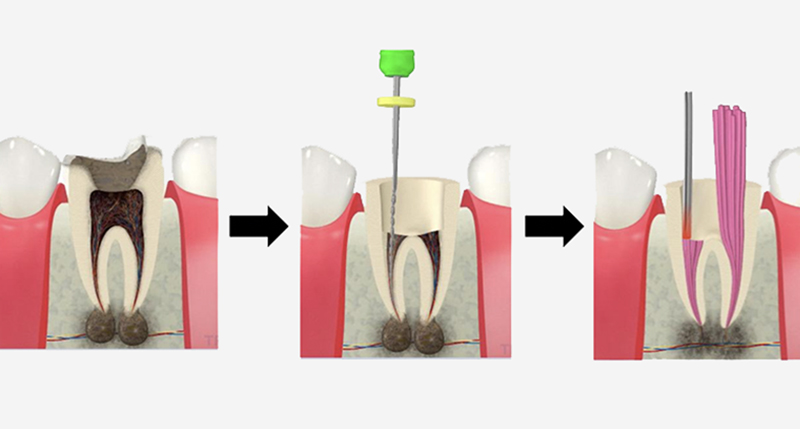

CT撮影

病気の有無、3次元的な根管の形を把握することができます。

正確な診断のためには必須ですが、

保険診療では大臼歯しか撮影することが

できません。

根管を墨汁で染め出した状態です。根管はこんなにも複雑な形をしています。

病変や根管の形、状態を3次元的に把握します

通常のレントゲン撮影では確認できない根や、根の先の炎症もCTによって確認することができます。